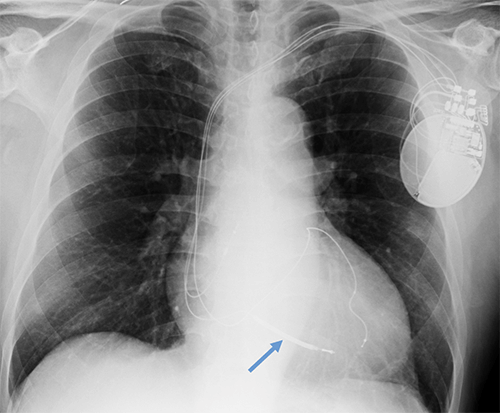

- CEID images with lead types:

Pacemaker with transvenous leads

Pacemaker with epicardial leads

Defibrillator lead

Subcutaneous defibrillator

Cut epicardial wires (often hard to see)

Abandoned leads

Abanded leads plus generator

Temporary transvenous lead

Leadless pacemaker